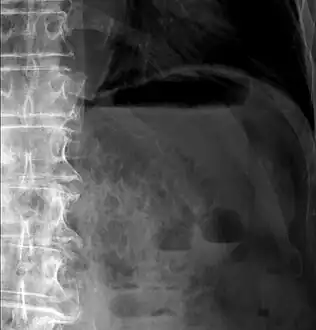

Upright AP radiograph showing gas in the wall of the small bowel in the left upper quadrant indicative of pneumatosis intestinalis.